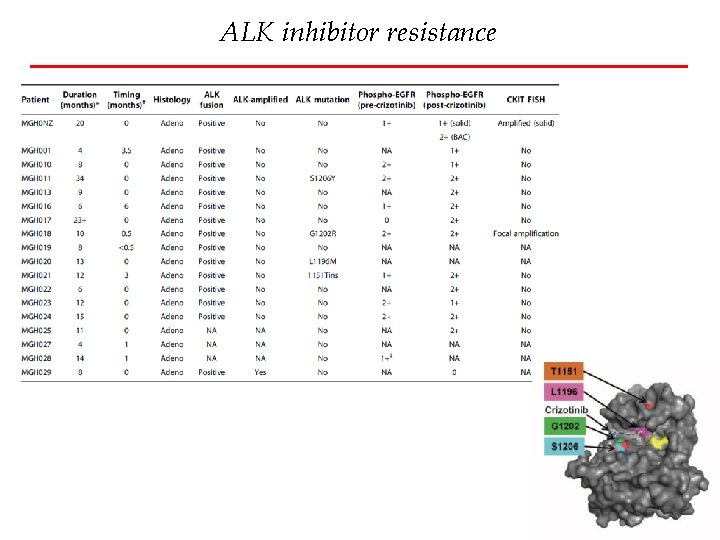

ALK inhibitor resistance